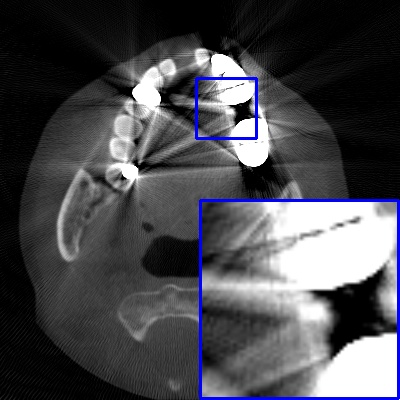

Figure 4: Comparison of MAR images by different methods on real-world MA image. The last image is the metal mask by selecting the pixel area over 2800HU in the MA image.

Results on real-world MAR. We also compare these methods on dental CBCT images with real-world metal artifacts. The visual results on one sample are shown in Fig. 4. We observe that our MARformer-T and MARformer-L well seperate the adjacent teeth and retain their shapes. This shows that our MARformers, though trained on synthetic data, are effective on real-world MAR.